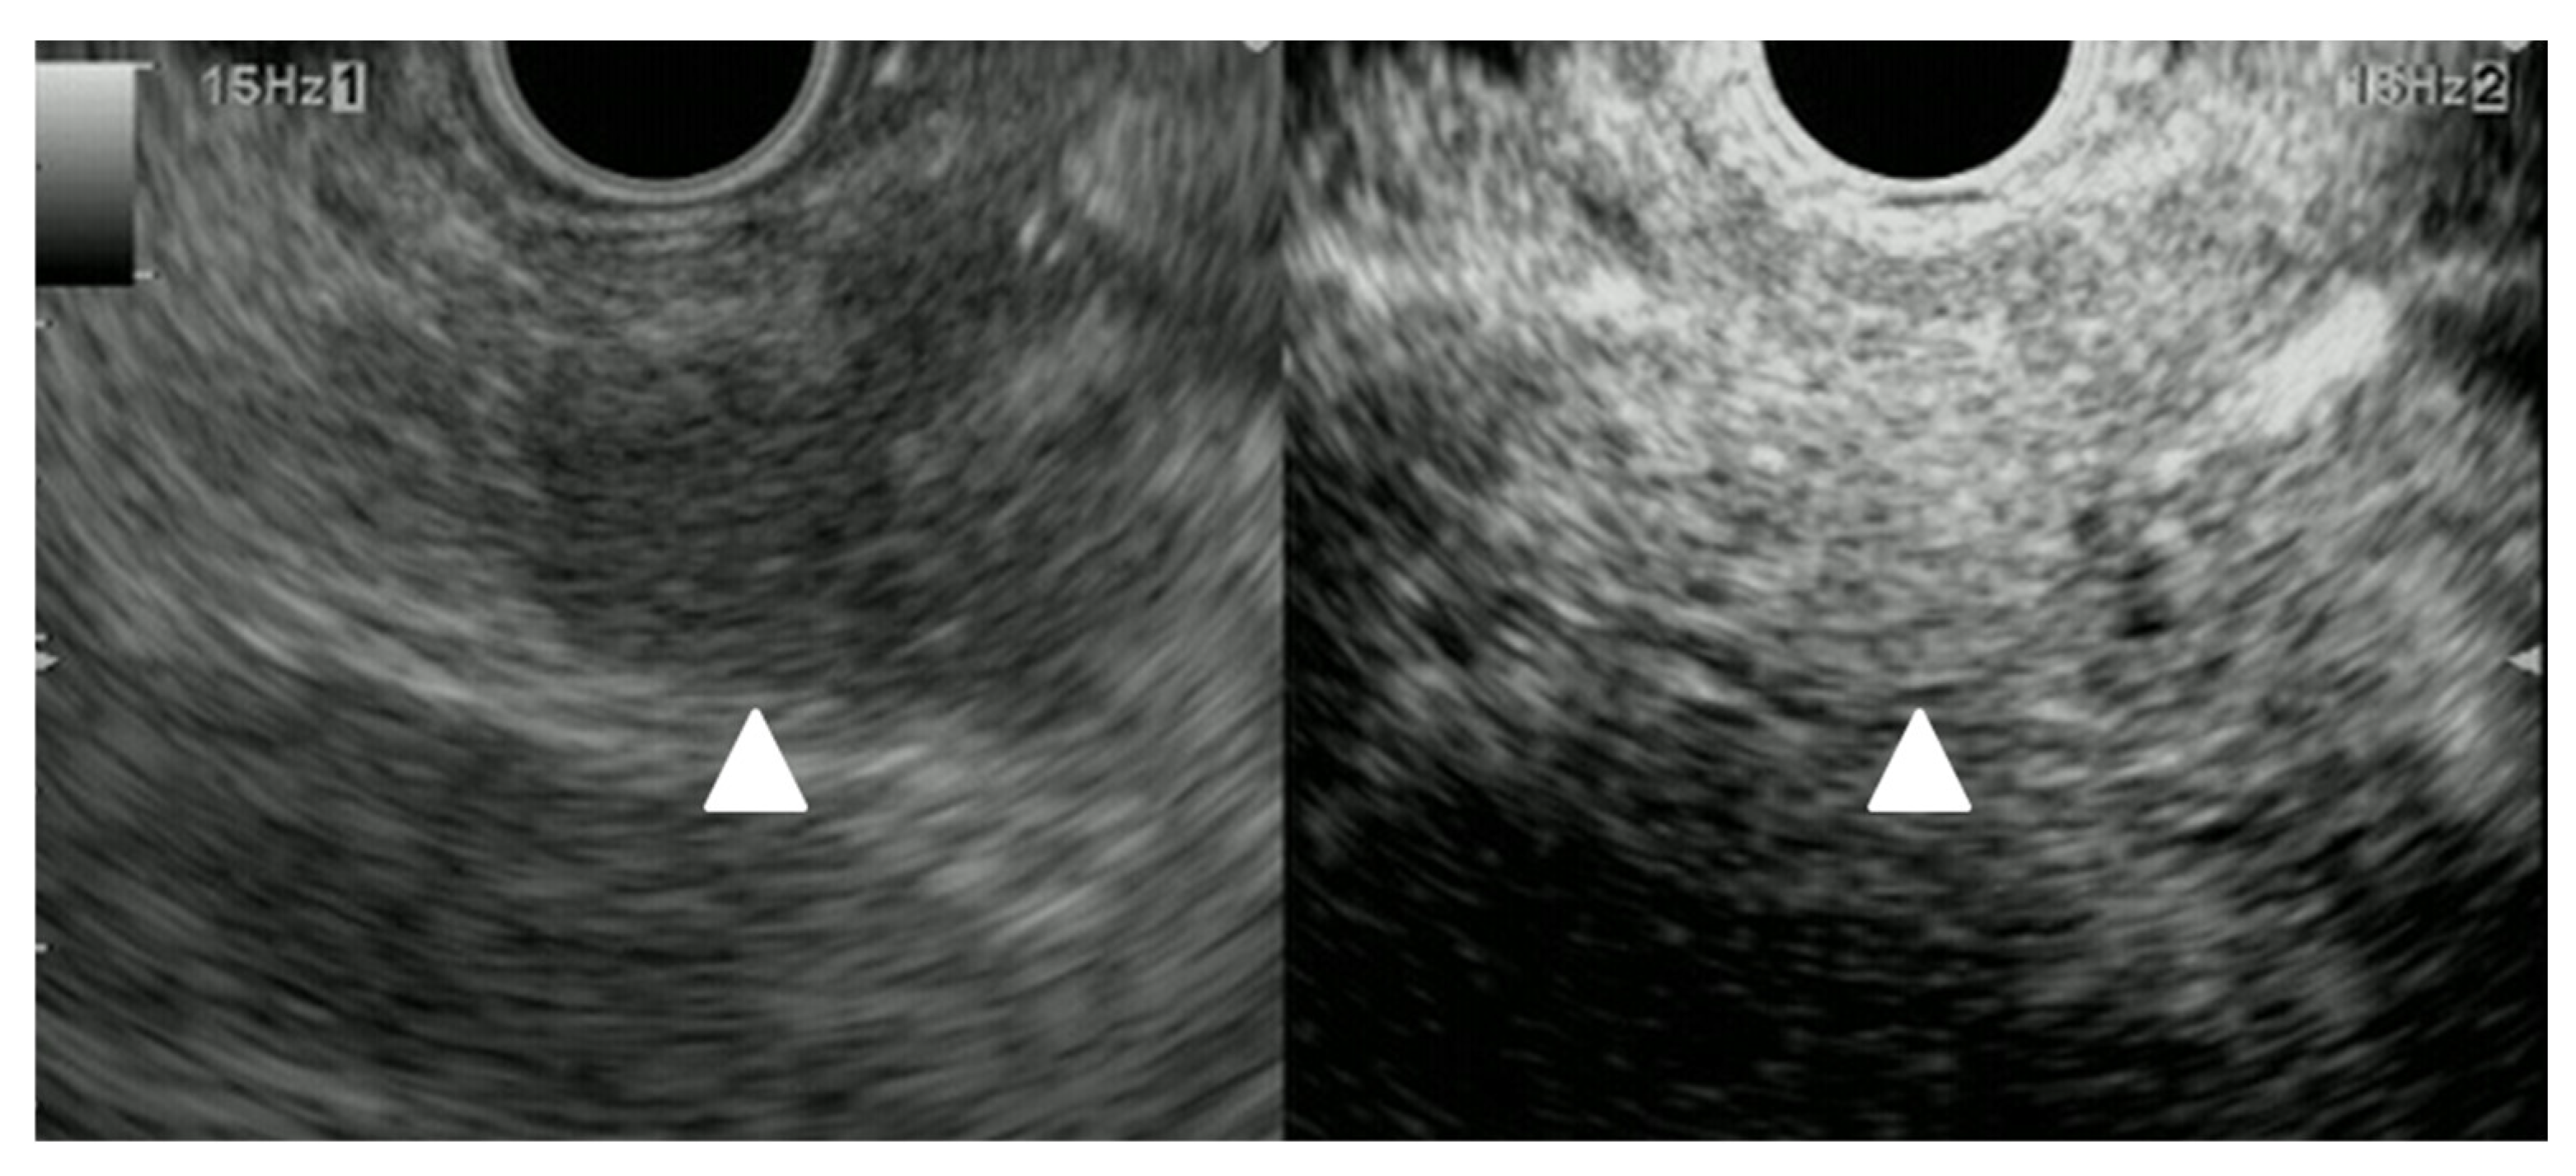

| Elastography (small lesions up to 15 mm) [67] | 41% softer or isoelastic, 59% stiffer compared to pancreatic parenchyma | 4% soft or isoelastic, 96% stiffer compared to pancreatic parenchyma | 64% soft or isoelastic, 36% stiffer compared to pancreatic parenchyma |